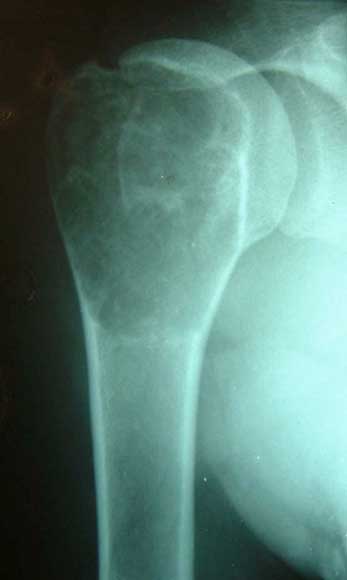

肱骨骨折,3次钢板和钢丝固定后失败。改用带锁髓内钉固定,4个月后骨折愈合。